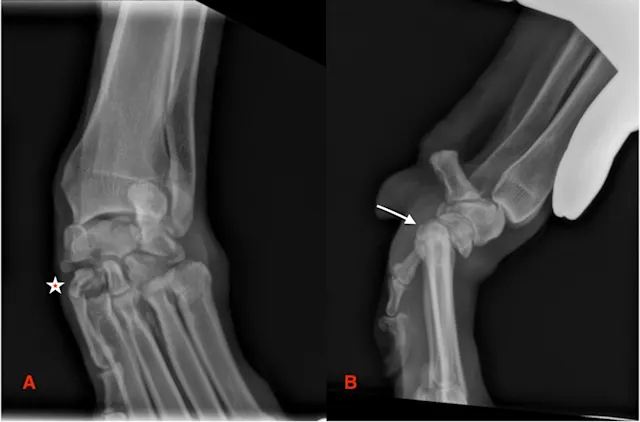

Examples of Radiographic Findings Associated With Carpal & Tarsal Injuries

(Figures 6-9)

FIGURE 6

Radiography was performed on a 10-year-old spayed rough collie with acute lameness of the left thoracic limb after chasing a cat. Stress was applied with the carpus in extension (A), flexion (B), valgus (C), and varus (D). Lateral (A, B) and dorsopalmar (C, D) views of the carpus are provided. Visible joint widening (C, asterisk) can be visualized between the radial carpal and second carpal bones, and a comminuted fracture of the proximal aspect of the second and third metacarpal bones is present (C, arrow).